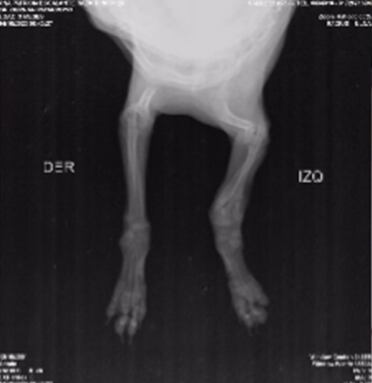

De acuerdo con Alejandra Prada, activista por los derechos de los animales en la capital santandereana, la perra habría sido arrojada desde un segundo piso y, tras el fuerte golpe, sufrió varias fracturas en sus paticas que le impiden moverse con normalidad.

“Sol es una pequeña bebé de tres meses que tiraron por un balcón y la abandonaron a su suerte.Las personas se fueron de la casa y la dejaron ahí solita y llorando. El golpe ocasionó que su patita esté totalmente partida, es una fractura que tiene muchas semanas, se imaginan el dolor y su sufrimiento”, dijo Alejandra Prada.

Ante la gravedad de la lesión, la perrita fue sometida a una cirugía. Sin embargo, el procedimiento aún no ha sido terminado en su totalidad y por ello, Alejandra hace un llamado a la comunidad para poder costear todos los gastos que implica el proceso de recuperación de la canina.

“Sol es una perrita demasiado noble y tierna, bajo mi cuidado estará bien y la sacaremos adelante. Quiero contarles que está en recuperación, controles y posteriores terapias para la movilidad total de su patita”, agregó Prada.